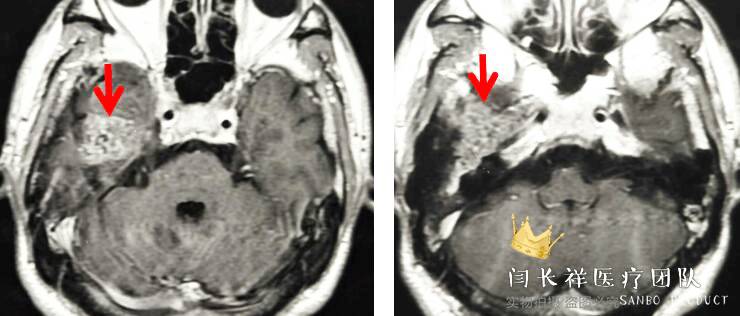

术前MRI轴位T1扫描示病灶呈等信号。

中颅窝-颞下窝占位

术前MRI轴位T2扫描示病灶侵及面神经膝段及中耳骨质。

术前MRI轴位T1增强示病灶显著不均匀强化。